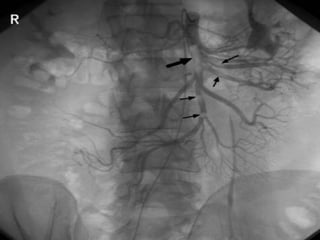

Angiography

It is the gold standard for

diagnosis of mesenteric vascular

occlusion.

63-year-old woman status post aortic valve replacement who presents with a one

week history of abdominal pain becoming quite severe over the last 24 hours.

Post OP - Diffuse vasospasm

without occlusions.

Post Papaverine infusion

Arteriogram 24 hr later.

Reversal of vasospasm.

63-year-old woman statuspost aortic valve replacement who presents with a one week history of abdominal pain becoming quite severe over the last 24 hours.

Post OP -Diffuse vasospasm without occlusions. Post Papaverine infusion Arteriogram 24 hr later. Reversal of vasospasm.